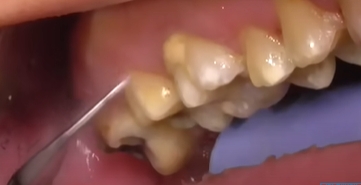

치석은 오랜 시간 쌓이면서 잇몸과 치아 사이를 가리고 있던 돌 같은 물질입니다. 이 치석이 갑자기 떨어지거나 스케일링으로 제거되면 그동안 가려져 있던 치아뿌리나 잇몸 틈이 드러나면서 공간(구멍)이 생긴 것처럼 보일 수 있어요.

이러한 치석 떨어짐으로 인한 구멍은 방치하면 더 큰 문제를 일으킬 수 있는데요. 이물질이 계속 끼고 충치나 잇몸염증으로 발전할 가능성도 높아지죠.

하지만 사실 구멍이 생겼다기보단 치석 아래에 있던 원래의 치아 구조가 드러난 것일 뿐이며 다만 이 공간이 음식물이나 세균에 노출되면 문제가 생기므로 그대로 방치하기보단 적절한 조치를 취하는 게 중요합니다.